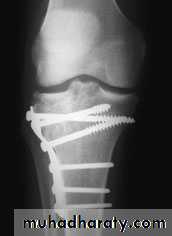

For displaced fracturestreatment is by open reduction and internal fixation with

plate and screws as it is an intra articular fracture.fixation of tibial plateau fracture

Complications :

1- Vascular injuries and nerve injuries.

2- Compartment syndrome (specially with severe condylar fractures).

3- Joint stiffness (prevented by early range of motion exercises).4- Deformity

(Varus or Valgus), Valgus deformity are common complication.5- Secondary osteoarthritis (due to residual depression, knee deformity or ligament instability) .